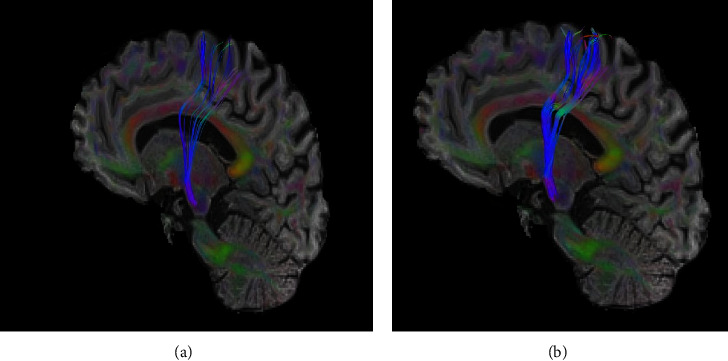

Results: After the application of DN, the mean FA of the ipsilesional CST increased from 0.35 to 0.39, concomitantly with a decline in aFA from 0.18 to 0.13. Notably, the rFA exhibited a pre-DN value of 0.69, which subsequently rose to 0.76 post-DN. Moreover, a significant reduction in MMAS scores was detected, from a score of "3" prior to DN application to a post-DN score of "1". In terms of wrist mobility, both active and passive extension ROM exhibited favorable improvements, with an increase of 12° for active extension and 16° for passive extension. Furthermore, there was a substantial improvement in the BBT score, an indicator of manual dexterity, ascending from 12 to 24.

Conclusion: Enhancements in CST consistency suggest it as a potential mechanism contributing to the observed improvements following DN in this stroke case.